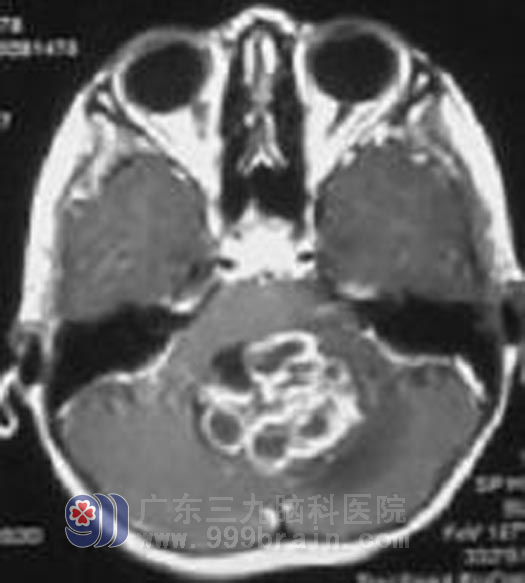

手术前

莹莹是广东兴宁的农村里可爱的小女孩,2006年10月就在莹莹刚满4岁的时候,小莹莹无征兆出现恶心呕吐,伴有头晕头痛,父母带着莹莹到当地最大的医院就诊,头颅CT显示为小脑蚓部占位,并伴梗阻性脑积水。焦急的父母立即带着莹莹到了广州的大医院治疗,很快小莹莹接受了颅脑手术,因为病理是毛细胞性星型细胞瘤WHOI级,归属于良性肿瘤,且手术后莹莹的恶心呕吐头痛头晕症状都消失了,小莹莹没有接受肿瘤的进一步放疗。之后也没有遵医嘱定期复查。不曾想到的是,手术后残留的肿瘤细胞还在小莹莹的颅内生长、繁殖、肆虐着。http://www.999brain.com/